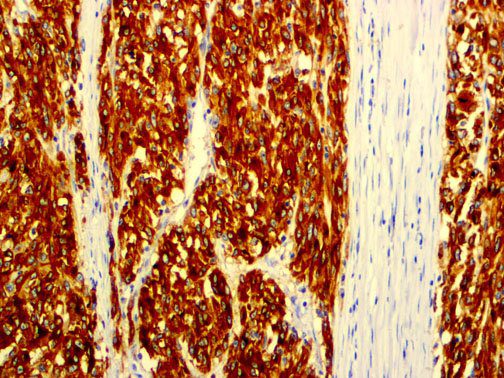

It is the ICU physician who is most likely to witness one of the deadliest manifestations of the abnormal immunological response, the cytokine storm syndrome (CSS). This response is also referred to by some as the cytokine release syndrome (CRS). CSS is characterized by continuous activation and expansion of macrophage and lymphocyte populations, which secrete large amounts of cytokines, causing the cytokine storm. This massive cytokine release is akin to hemophagocytic lymphohistiocytosis (HLH) disease, a syndrome characterized by initial unchecked and persistent activation of cytotoxic T lymphocytes and NK cells.

Clinical and laboratory manifestations of HLH include fever, enlarged liver and/or spleen, neurologic dysfunction, coagulopathy, liver dysfunction, cytopenias (i.e., low levels of erythrocytes, leukocytes, and/or platelets), hypertriglyceridemia, hyperferritinemia, hemophagocytosis, and eventually diminished NK cell activity as the immune system becomes progressively paralyzed. HLH can be familial (primary HLH) or secondary to another disease process (sHLH), such as rheumatic disease, in which it is referred to as macrophage activation syndrome (MAS, characterized by elevated ferritin).